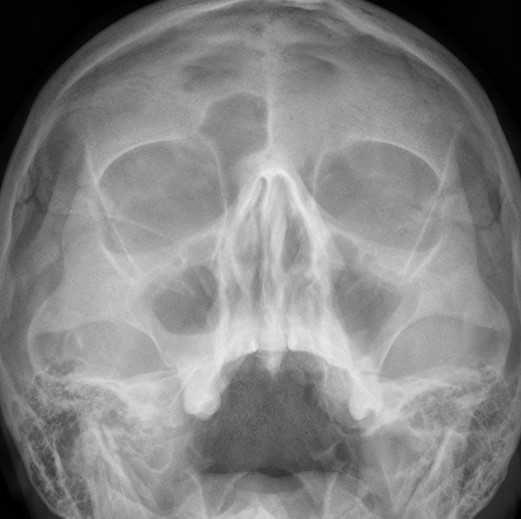

Простой синуслифтинг. Часть I.